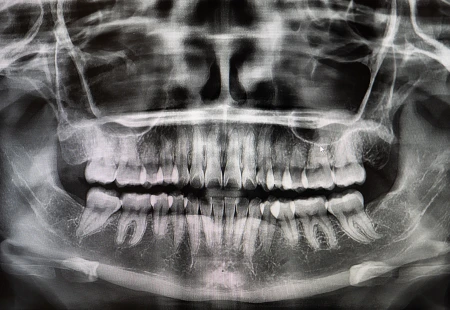

How do we know if there is decay (a cavity) between the teeth when it’s not visible to the naked eye? X-rays are one of the most valuable tools in the diagnostic process. We cannot “see” cavities between teeth without the help of digital x-rays. During your cleaning and check-up visits, we may take “bitewing radiographs”, “periapical radiographs”, or a “full mouth series”, depending on your specific needs. These images allow us to visualize between the teeth and around the roots of the teeth to check for cavities, bone loss, tartar build up, and pathology.

Digital x-rays become even more important to check for tooth decay when a patient is not flossing or cleaning between the teeth regularly. It is always best to identify and treat cavities before they become painful, so you can avoid a dental emergency.

Radiology is a critical tool in the diagnosis of oral pathology. By taking panoramic style radiographs and 3D CBCT images, we are able to visualize potential bony pathology in the jaws, sinuses, and around the teeth. By maintaining records of your x-rays over time, we are able to quickly identify changes that may be cause for concern. At Garden Ridge Center for Dentistry, we use x-ray technology to treat our patients in a safe and comprehensive manner.